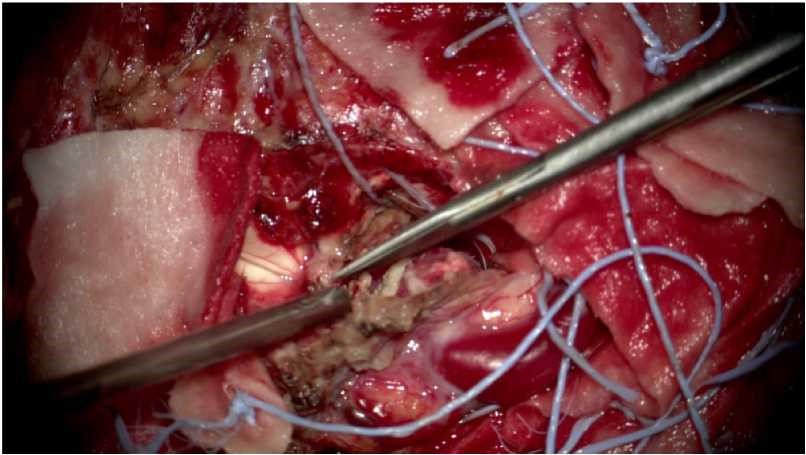

术中情况:

2、AVM切除应找到供血动脉的源头,尽量全切,否则会出现复发。

3、AVM切除不一定将周围脑组织一并切除,可以选择将畸形血管团与周围脑组织剥离开后切除。